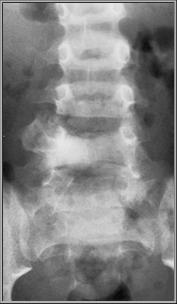

Osteoblastoma